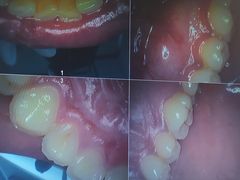

• 牙博士口腔品牌连锁(杨浦店)

• -牙博士口腔品牌连锁(杨浦店)

日料与海鲜共舞 | 21-03-03